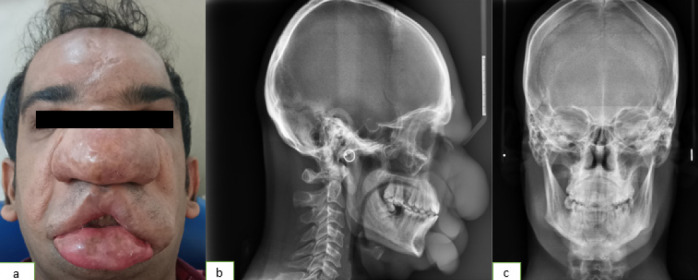

Rhinoentomophthoromycosis: An Enigma in Itself

{"title":"Rhinoentomophthoromycosis: An Enigma in Itself","authors":"Smrithy Sivadas K, Renita Lorina Castelino","doi":"10.4274/balkanmedj.galenos.2025.2024-12-7","DOIUrl":null,"url":null,"abstract":"","PeriodicalId":8690,"journal":{"name":"Balkan Medical Journal","volume":" ","pages":"369-370"},"PeriodicalIF":3.8000,"publicationDate":"2025-07-01","publicationTypes":"Journal Article","fieldsOfStudy":null,"isOpenAccess":false,"openAccessPdf":"https://www.ncbi.nlm.nih.gov/pmc/articles/PMC12240223/pdf/","citationCount":"0","resultStr":null,"platform":"Semanticscholar","paperid":null,"PeriodicalName":"Balkan Medical Journal","FirstCategoryId":"3","ListUrlMain":"https://doi.org/10.4274/balkanmedj.galenos.2025.2024-12-7","RegionNum":4,"RegionCategory":"医学","ArticlePicture":[],"TitleCN":null,"AbstractTextCN":null,"PMCID":null,"EPubDate":"2025/3/28 0:00:00","PubModel":"Epub","JCR":"Q2","JCRName":"MEDICINE, GENERAL & INTERNAL","Score":null,"Total":0}